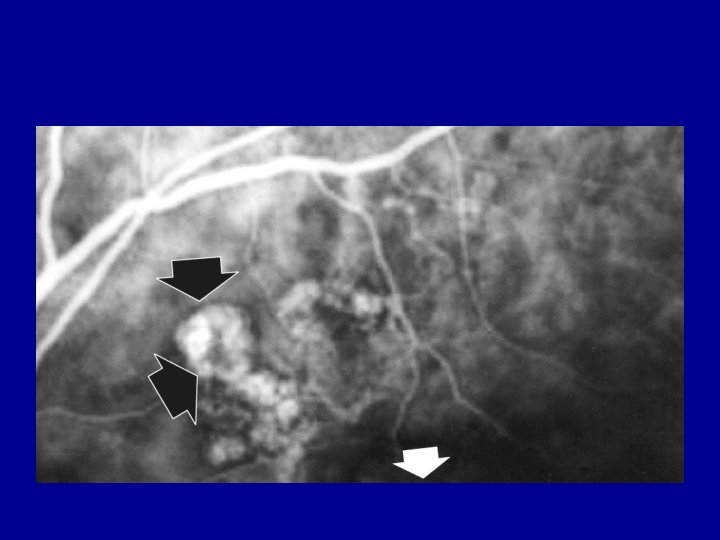

Polypoidal choroidal vasculopathy • • • Sub type of AMD 15% of all ‘CNV’

Polypoidal choroidal vasculopathy • • • Sub type of AMD 15% of all ‘CNV’ Steep walled haemorrhagic PED on OCT PDT +/- anti VEGF best Need ICG to diagnose most (wide angle to pick up more)